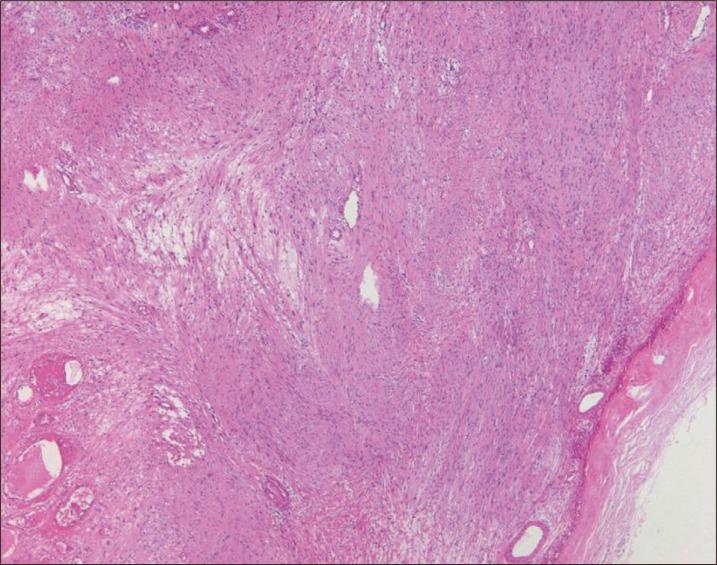

腮腺内面神经鞘瘤

Intraparotid Facial Nerve Schwannoma.

Intraparotid facial nerve schwannoma is a rare benign neoplasm. Due to its rarity, it is not usually a prioritized diagnosis before surgery and may therefore lead to an unintentional treatment error. In this article, we report a single case of intraparotid facial nerve schwannoma. We were able to make a diagnosis with frozen biopsy. A complete resection of the mass while preserving the facial nerve was performed. Herein we present our clinical experience with regards to the treatment process of intraparotid facial nerve schwannoma.

摘要

腮腺内面神经鞘瘤是一种罕见的良性肿瘤。由于其罕见性,术前通常不会将其列为优先诊断,因此可能导致无意的治疗失误。在本文中,我们报告了一例腮腺内面神经鞘瘤病例。我们通过冰冻活检做出了诊断。在保留面神经的同时对肿块进行了完整切除。在此,我们介绍我们在腮腺内面神经鞘瘤治疗过程中的临床经验。